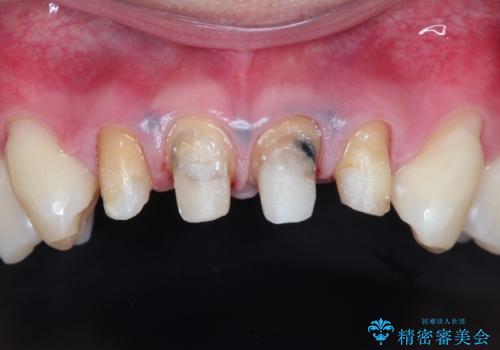

- 上の前歯の見た目が気になるとのことで来院されました。

上の前歯の4本が神経の処置がされており、前から2番目の歯が内側に入り込んでしまっていました。

また、金属で治療された根本の歯茎が黒く変色(メタルタトゥー)しており、余計に見た目がよくない状態となっておりました。